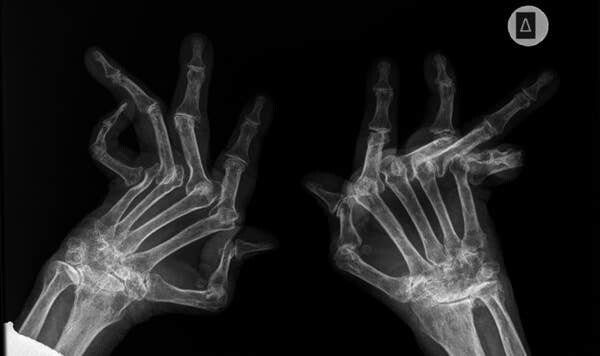

6. Вот рентгеновский снимок, показывающий, насколько тяжелым может быть артрит